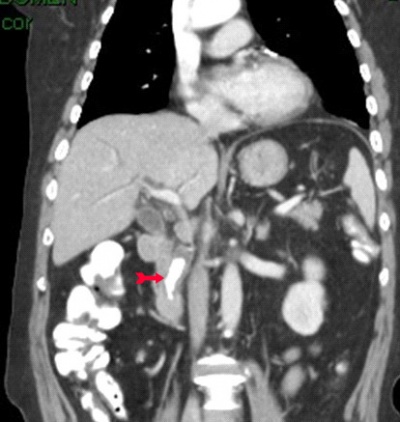

ב- CT המבוצע לחולים אלה במסגרת בירור כאבי בטן אפשר לראות הרחבה של דרכי המרה (תצלום 33.8) וכן אבנים בדרכי המרה (תצלום 34.8 ) למרות שאין זו בדיקת הבחירה לאבנים בדרכי המרה.